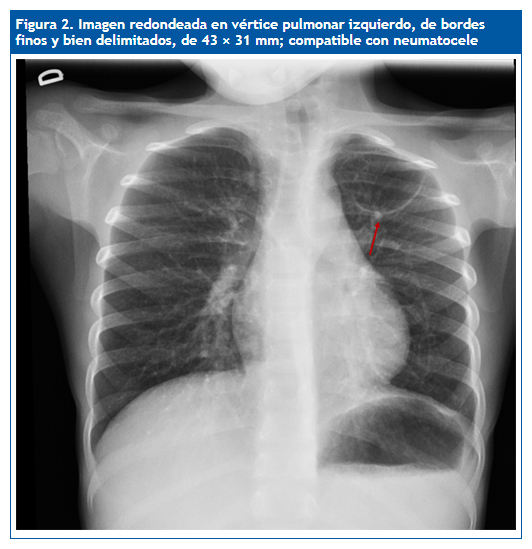

En la revisión 50 días más tarde se aprecia la resolución completa de la consolidación neumónica y una imagen elíptica de 4,3 × 3 cm en el vértice superior izquierdo compatible con neumatocele (Fig. 2). Se opta por tratamiento conservador. En una nueva placa realizada tres meses después se observa una imagen similar, y cuatro meses más tarde (nueve tras diagnóstico inicial) se aprecia, en la radiología torácica convencional, la desaparición de la imagen previa, lo que demuestra resolución espontánea y confirma la sospecha inicial de neumatocele.

| Figura 2. Imagen redondeada en el vértice pulmonar izquierdo, de bordes finos y bien delimitados, de 43 × 31 mm; compatible con neumatocele |